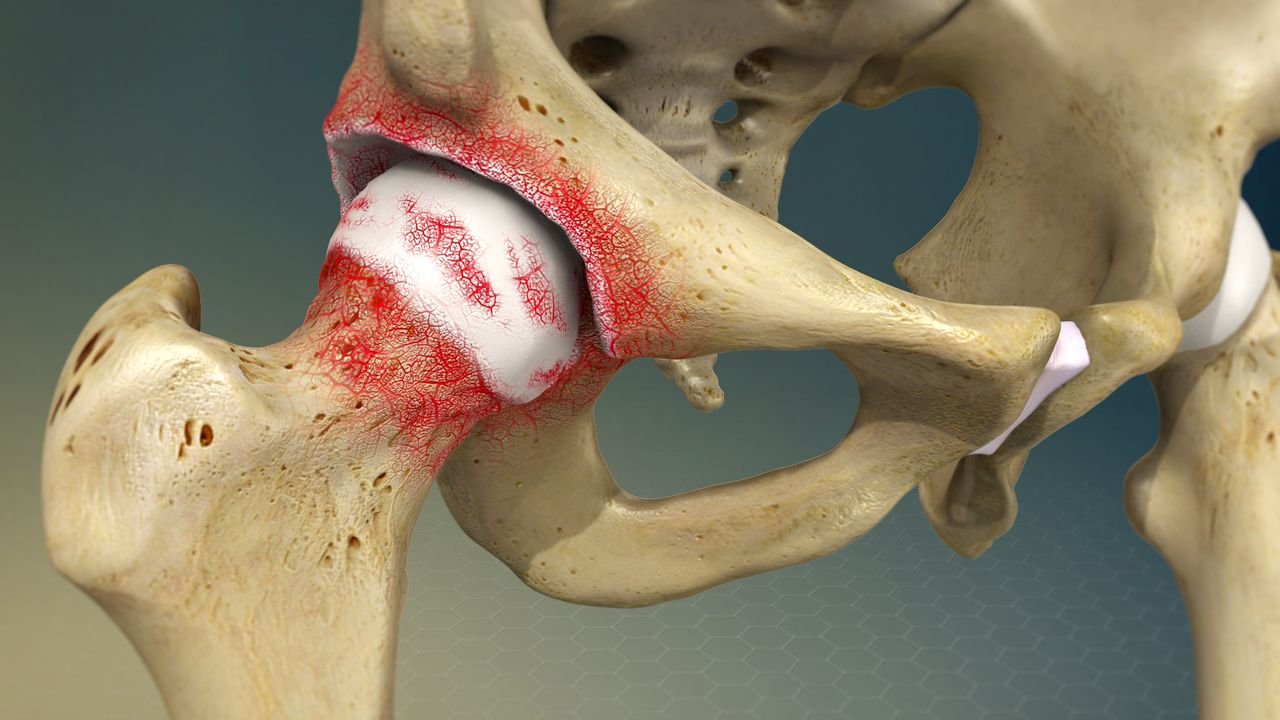

Total Hip Replacement is executed when your hip joint is injured and all other treatment options have failed. The damaged bone and cartilage are removed during the treatment and replaced with a prosthetic socket on the hip bone and a ball on the thigh bone. Natural bone growth over time holds the hip joint in place.

Arthritis is the most common cause of hip discomfort. There are different types of arthritis that can damage the hip joints, and the following are the most common disorders that necessitate hip replacement surgery.

Osteoarthritis

Osteoarthritis is the "wear and tear" that occurs when your joints are overworked. It normally occurs with age, but it can also be caused by joint traumas or obesity, which puts more strain on your joints.

It most commonly affects weight-bearing joints such as your knees, hips, foot, and spine. It frequently develops gradually over months or years. It causes pain in the afflicted joint.